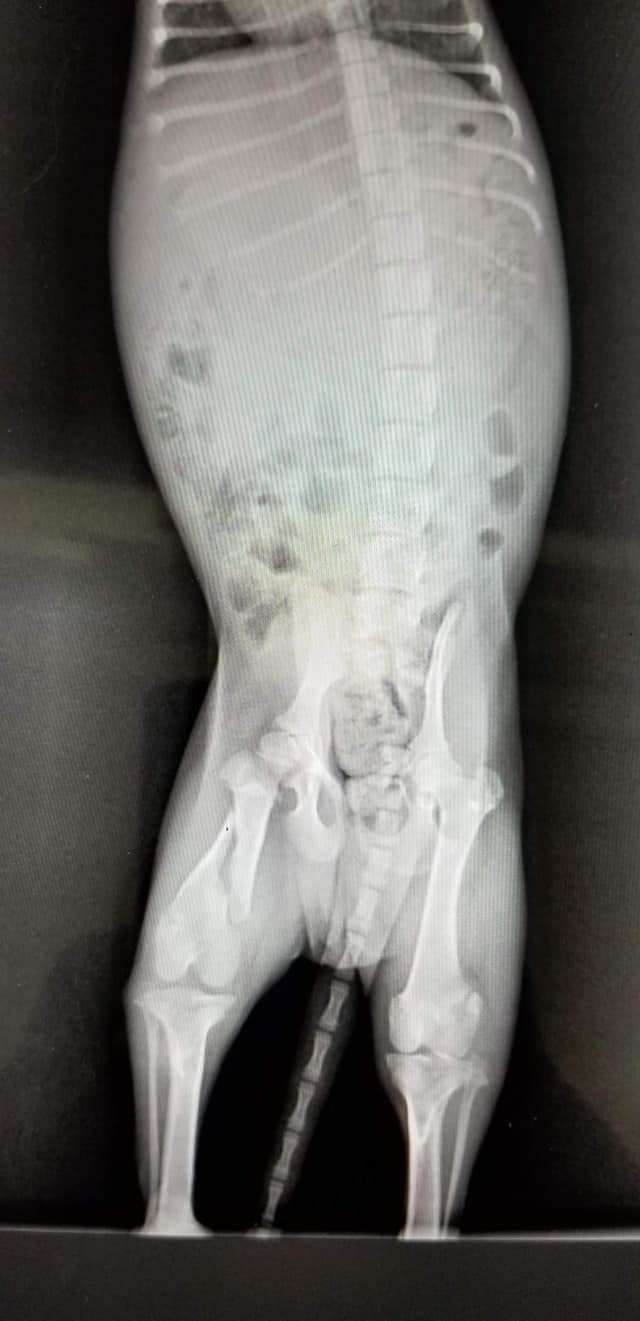

Staff also found that pup had a broken leg as well which required surgery. They believed that someone might have thrown him top of the bridge and pup barely missed the water as he landed on the ground.